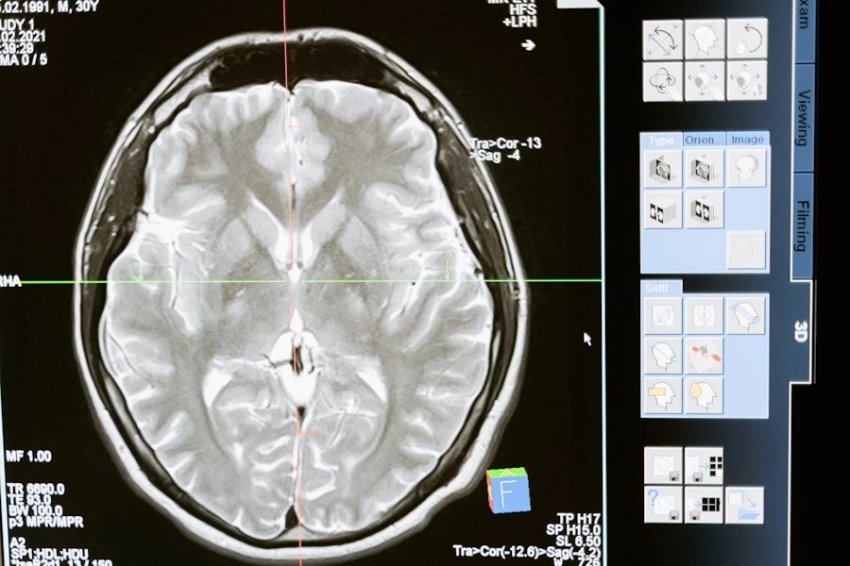

Благодаря нейроинтерфейсам они посредством мысли смогут управлять протезами, контролировать инвалидные коляски, работать с гаджетами. Сейчас ведутся исследования по применению мозговых чипов для лечения эпилепсии, болезни Паркинсона, слепоты и других заболеваний.

По мнению специалистов компании Neuralink, технология Link позволит не только управлять протезами конечностей, но и совершит революцию в лечении определенных заболеваний, таких как ожирение, аутизм, депрессия, шизофрения и последствия повреждений спинного мозга.